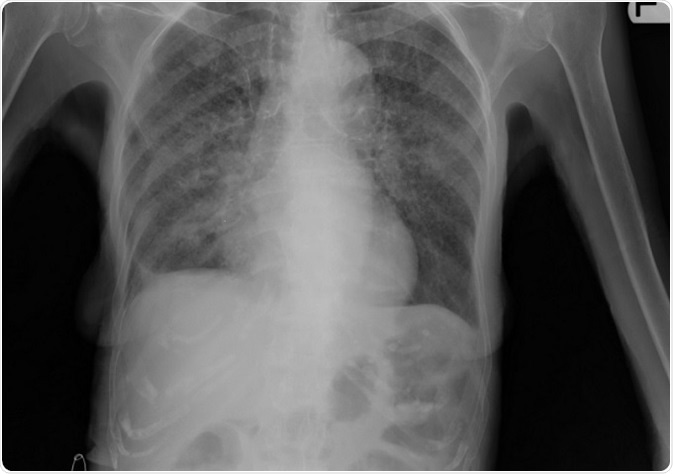

In this type of tuberculosis the lesion more often than not lies in the lungs. A Chest X ray shows the lesion within the lungs. There may be scarred appearance of the lungs.

Image: Lung X-ray of patient with tuberculosis. Credit: Yale Rosen/ flickr.com. Shared under the license.

Primary tuberculosis usually appears in the central upper portion of the lungs with a pleural effusion or collection of fluid around the lungs. In severe disease there may be a picture like millet seeds over the X ray plate of the lungs. This is called milliary tuberculosis.